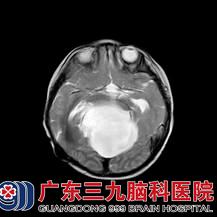

患儿2岁时,父母带其到广东三九脑科医院进一步治疗。入院后医生查体,发现洋洋不会说话,颈部无力,不能独自站立;头部磁共振提示:小脑上池巨大蛛网膜囊肿,脑干受压明显移位。

头部核磁显示小脑上池巨大蛛网膜囊肿,压迫脑干向前方意外,堵塞中脑导水管。

术后复查头部磁共振,显示原蛛网膜囊肿及脑室系统明显缩小,脑干受压症状得到明显缓解。洋洋住院10天,拆线后已痊愈出院。目前患儿生长发育正常,已随访1年,未见复发。